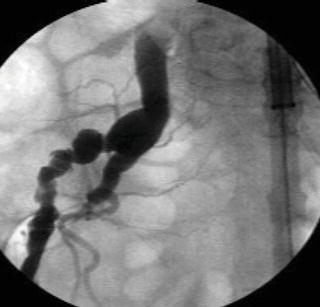

Retrograde percutaneous access of the common femoral artery is performed with an 18 gauge needle in the usual fashion and a 0.035 inch glide wire is advanced under fluoroscopic guidance into the distal thoracic aorta after heparin is administered. A 9 Fr sheath is then exchanged for the needle. A retrograde angiographic picture of the iliac vessels is performed noting the size, tortuosity, and calcification. The presence of a small, or severely calcific or tortuous, iliac vessel may preclude the introduction of a delivery sheath (Fig. 1.5). An attempt may be made to pass the delivery sheath, and if any resis tance is noted the patient would require a retroperitoneal conduit or an endoconduit. Using the existing 9 Fr sheath, balloon angioplasty can be performed to gently dilate the vessel; subsequently, an endoluminal graft, most commonly (Viahbahn; W.L. Gore & Associates, Flagstaff, AZ), or an I-Cast stent-graft (Atrium Medical, Hudson, NH) (Table 1.1) is deployed across the common iliac and external iliac artery covering the hypogastric vessels (Fig. 1.6). Post-deployment balloon angioplasty is subsequently performed with a balloon to expand the endoluminal graft; this technique has been referred to as cracking and paving. The 9 Fr sheath is subsequently exchanged to a 20–24 Fr delivery sheath that is required to deliver the thoracic endoluminal graft.

Fig. 1.5 Angiogram demonstrating a small, tortuous left iliac artery.

Attempts to introduce a delivery sheath in a small, tortuous, or calcified artery, or a combination, will lead to rupture of the access vessel typically at the junction of the external and internal iliac artery or at the aorto-iliac bifurcation. Rupture of an access vessel should be suspected if there is a drop in the blood pressure during advancement of the delivery sheath or during removal of the delivery sheath. The guide wire should be maintained at all times prior to removal of a delivery sheath and an iliac angiogram performed prior to removal of the introducer sheaths to confirm extravasation of contrast (Fig. 1.11a). Once rupture is confirmed, an appropriate length and diameter of a covered stent-graft should be chosen (Fig. 1.11b) and deployed across the area of rupture (Fig. 1.11c). In most instances coverage of the hypogastric artery is required.

Fig. 1.11 (a) Angiogram demonstrating rupture of the right external iliac artery. (b) A covered stent-graft used to exclude the site of rupture. (c) A covered stent-graft deployed across a ruptured iliac artery.